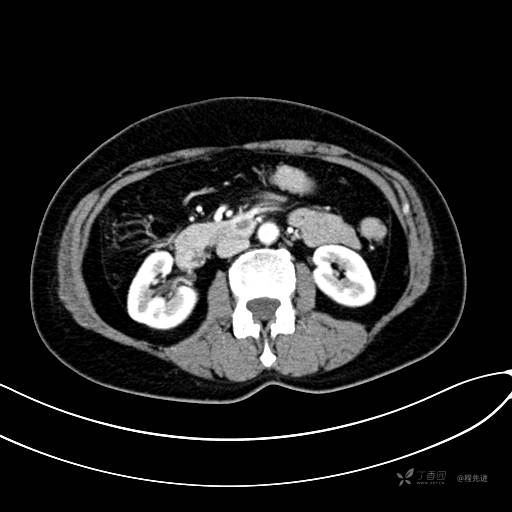

CT平扫